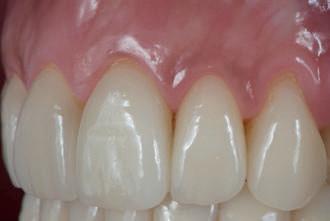

MARÇO 2011 MARÇO 2017

Os tecidos periodontais permaneceram saudáveis (ver Fig. 5) ao longo destes anos, talvez até mais saudáveis do que se a paciente tivesse permanecido com o seu esmalte original, já que a cerâmica feldspática retém menos placa bacteriana que o próprio esmalte2,10. Contribui também para esta sanidade gengival, o facto de a adaptação marginal de uma faceta feldspática ser melhor do que a de outros tipos de restaurações indiretas nomeadamente nas coroas tradicionais cimentadas (em vez de aderidas)11. Com a técnica do modelo refratário utilizada nestas facetas, consegue-se um “gap” de apenas 40 micra11. Além disso, estas restaurações são aderidas ao dente segundo o protocolo recomendado por Pascal Magne, que utiliza compósito micro-híbrido fotopolimerizável aquecido em conjunto com adesivo com carga (Optibond FL), em vez de usar cimentos resinosos, o que proporciona a preservação da qualidade na transição dente-restauração ao longo do tempo, quer a nível estético, quer a nível de rugosidade e de menor desgaste da superfície desse material que preenche o referido “gap”4 .